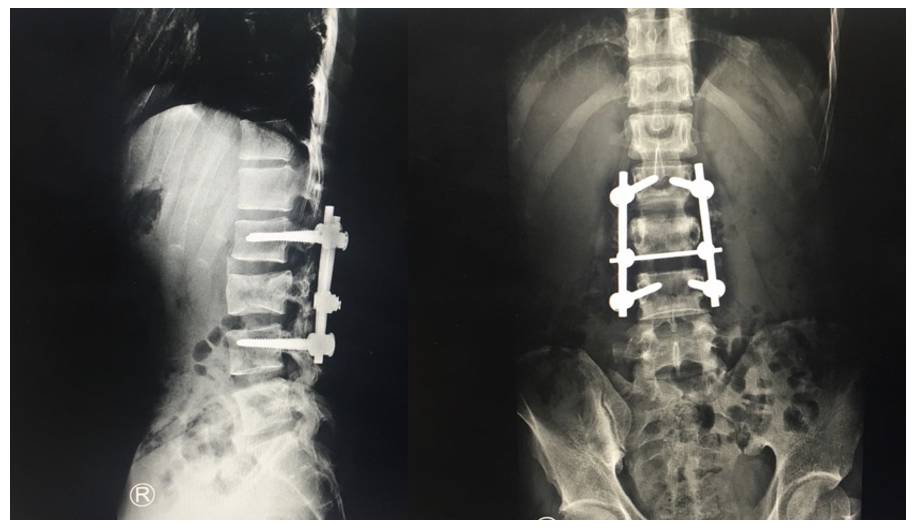

- ปี 2018 ได้รับอุบัติเหตุทางรถยนต์ส่งผลให้กระดูกสันหลังส่วนเอวข้อที่ 3 แตกหัก ได้รับการผ่าตัดใส่เครื่องมือยึดข้อกระดูกสันหลังส่วนเอวข้อที่ 2 และ 4